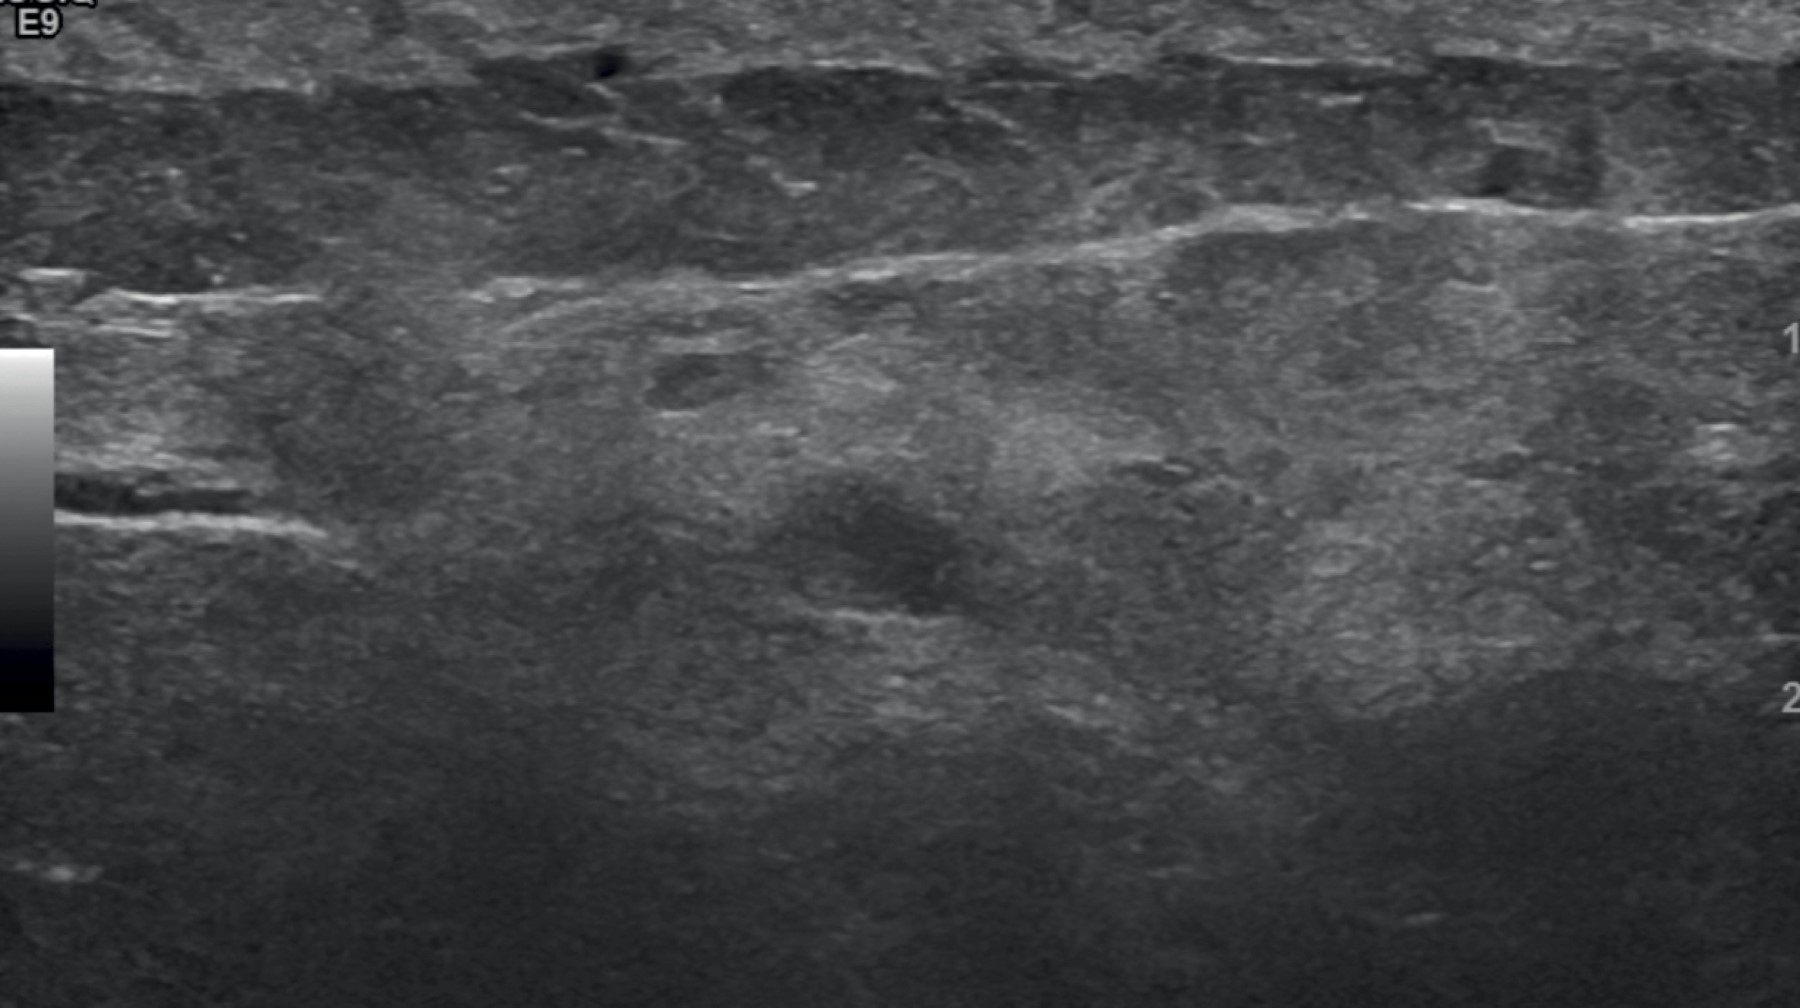

Figure 1

Figure 2

Figure 3

Figure 4

Figure 5